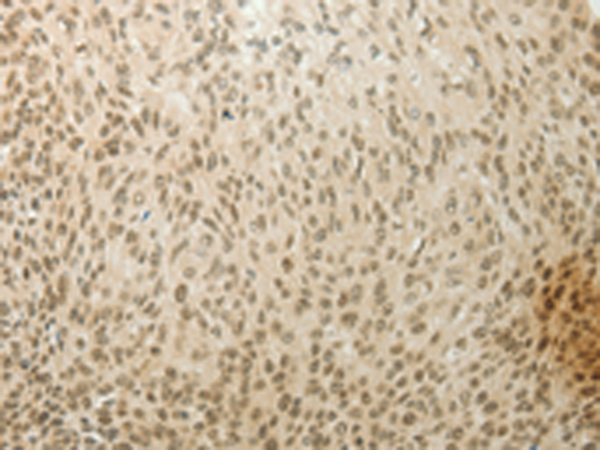

分类: 科研抗体货号: P11270别名: 2ADUB, 2A-DUB, RP4-592A1.1应用: WB,IHC反应种属: Human, Mouse